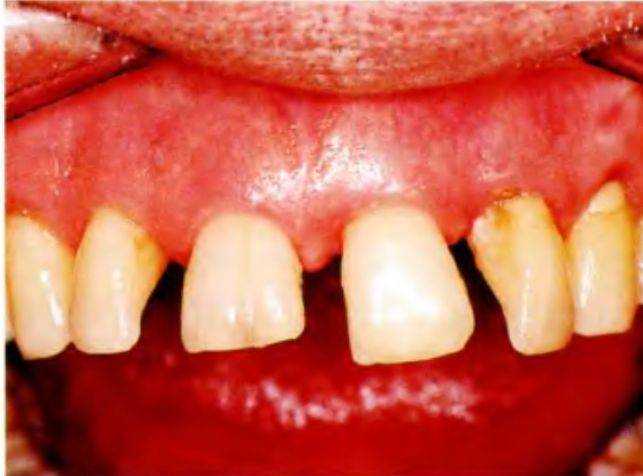

Рис. 6-43а {слева). Срединная линия и горизонтальные плоскости негармоничны

Рис. 6-43Ь (справа вверху). Плоскость, проходящая через уголки рта, негоризонтальна

Рис. 6-43с (справа внизу). Положение и наклон передних зубов затрудняют достижение высокого эстетического результата

ной линии (например, кривой нос или смещенный подбородок); асимметрией межзрачковой линии (в случае расположения глаз на разном уровне); скошенной мышечной линией (при расположении уголков рта на разном уровне); деформацией губ.

Кроме того, могут быть и другие эстетические проблемы (рис. с 6-43а по 6-43с): скошенная окклюзионная плоскость; скошенные оси зубов; диастемы; скученность передних зубов; протрузия зубов; ретрузия зубов; несимметричный контур зубов (особенно проблематичный при наличии десневой улыбки).